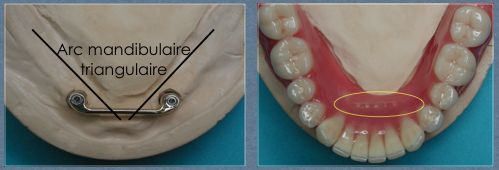

Dans cette situation, une barre de type Dolder compense plus efficacement ce porte à faux, le profil ovoïde de cette barre s’opposant plus efficacement à la bascule antérieure :

Il est donc préférable dans ces situations de concevoir une barre : la barre est orientée au laboratoire selon un axe d’insertion prothétique adapté, en l’occurence légèrement vers l’avant :

Il est par ailleurs important dans le cas d’une barre réduite au secteur antérieur de conserver un appui palatin de la prothèse afin d’avoir une sustentation verticale plus efficace et de diminuer les stress mécaniques sur la barre antérieure en cas de pressions importantes au niveau des molaires (photo de gauche).

Si la barre est étendue sur toute l’arcade (photo de droite) le palais pourra alors être supprimé car la prothèse sera totalement implanto-portée.